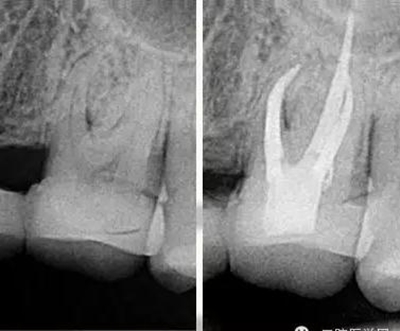

我喜歡比較有挑戰(zhàn)的工作,在牙科治療中最有挑戰(zhàn)的治療之一就是根管治療。牙齒的根管系統(tǒng)非常復雜,就像一顆大樹,有主干也有枝葉,要把這么復雜的根管系統(tǒng)治療到位很有挑戰(zhàn)。它需要掌握的技術(shù)比較多,涉及到的器械是最多的,治療一顆牙常常需要擺出3大桌的工具。當你花了很長時間把一顆牙的根管治療治療到位以后,看著術(shù)后的X線片,感覺就像在欣賞一件藝術(shù)作品,非常美,非常有成就感。

把根管感染清理出來,除了旋轉(zhuǎn)鎳鈦器械的切屑往外帶出來以外還有一些殘留的碎屑粘在根管壁上,要把這部分碎屑沖出來,就會用到根管超聲器械或者聲波器械,通過高頻震動,帶動根管內(nèi)部沖洗液的震動,從而讓那些殘留碎屑從根管壁上脫落下來并且被沖出來。好了,現(xiàn)在根管內(nèi)部都清理干凈了,剩下這個空腔我們要把它完全的填起來,不讓外界的細菌進入內(nèi)部。這個時候我們會用到一種材料叫牙膠,這種材料比較穩(wěn)定,可以長期的存在根管里?,F(xiàn)在比較先進的牙膠充填是熱牙膠充填系統(tǒng),把牙膠加熱到一定溫度后具有流動性,通過垂直加壓,讓它自動的把整個根管系統(tǒng)都填滿。